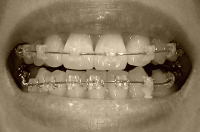

下顎は、左の3番が起き上がって5番が見えてきたので、ようやくブラケットが付きました。

これで、全部の歯にブラケットが付いたことになります!

下顎の右側は前回と同じく、パワーチェーンで4番の抜歯痕を埋めていくようです。

上顎。ワイヤー交換もありませんでした。

今後は、正中が合ったらラインを整えて、その後に内側に引っ込めていくとのことです。

そうか、まずは正中か!!